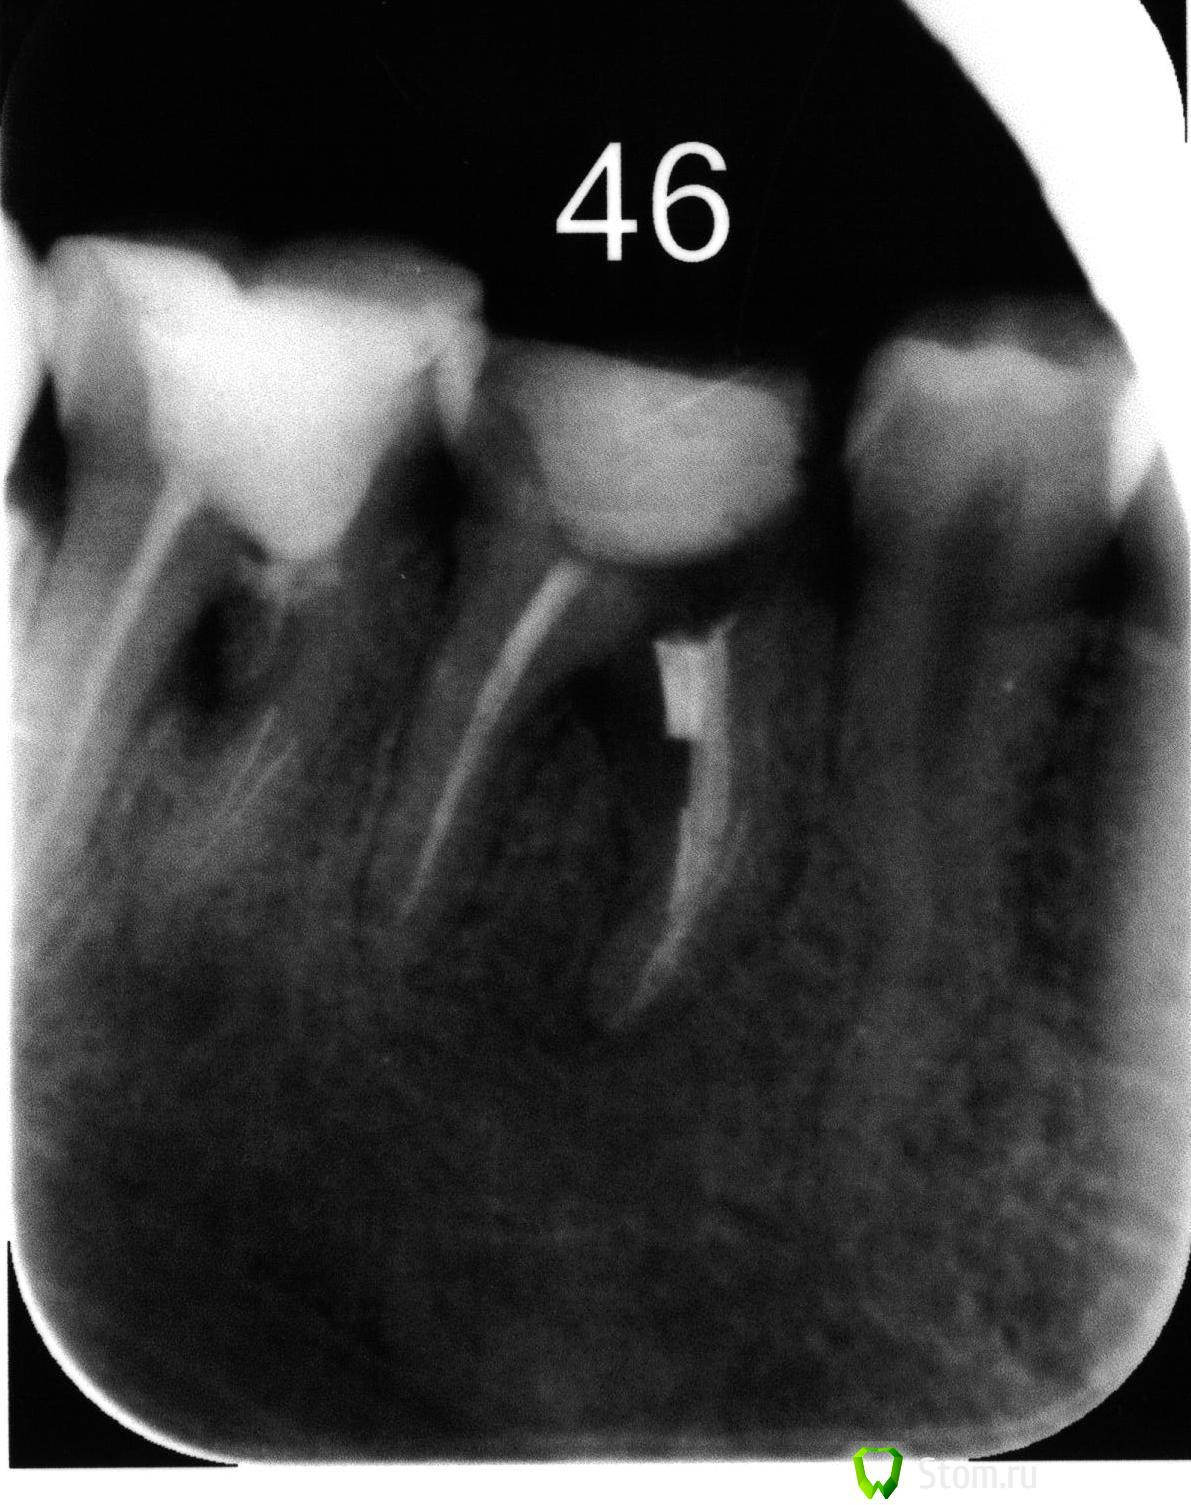

maryakma Опубликовано 23 марта, 2012 Поделиться Опубликовано 23 марта, 2012 Уважаемые специалисты, прошу вашей консультации по поводу дальнейшего лечения. При чистке каналов, кусочек инструмента отломился и застрял в канале. Попробовали его «выбить» каким-то специальным сверлом с ультразвуком. Часть удалось извлечь, но в итоге часть канала была разрушена (или раздроблена, что-то в этом роде). Потом несколько раз закладывали в канал лекарство, которое наращивает костную ткань (прорут, если не ошибаюсь). Но на фоне постоянного приема варфарина (снижение свертываемости крови), костная ткань не нарастает. Плюс ко всему одна из стенок зуба отломилась. Сейчас предлагают вариант сделать мост (опто-волоконный ? ), удалив один канал у этого зуба и у соседнего, плюс использовать соседний здоровый зуб, также предварительно рассверлив и запломбировав каналы в нем. Меня естественно все эти операционные вмешательства пугают как класс =( Подскажите пожалуйста как по вашему мнению, есть ли альтернативные варианты восстановления зуба? Понимаю, что по рентгену сложно учесть все факторы. Но может у кого-то были подобные случаи с положительным исходом. Заранее спасибо. Ссылка на комментарий

shishok Опубликовано 28 марта, 2012 Поделиться Опубликовано 28 марта, 2012 Дело не в пломбировке канала,а в том,что "продырявлена"насквозь стенка канала в обоих зубах.Это вызвало воспаление костной ткани.Улучшения не будет,а костная ткань будет со временем убывать. Ссылка на комментарий

Salma Опубликовано 23 марта, 2012 Поделиться Опубликовано 23 марта, 2012 Боюсь,что и 46 и 47 зубы подлежат удалению Ссылка на комментарий

Magdalena Опубликовано 25 марта, 2012 Поделиться Опубликовано 25 марта, 2012 (изменено) Уважаемые специалисты, прошу вашей консультации по поводу дальнейшего лечения. При чистке каналов, кусочек инструмента отломился и застрял в канале. Попробовали его «выбить» каким-то специальным сверлом с ультразвуком. Часть удалось извлечь, но в итоге часть канала была разрушена (или раздроблена, что-то в этом роде). Потом несколько раз закладывали в канал лекарство, которое наращивает костную ткань (прорут, если не ошибаюсь). Но на фоне постоянного приема варфарина (снижение свертываемости крови), костная ткань не нарастает. Плюс ко всему одна из стенок зуба отломилась. Сейчас предлагают вариант сделать мост (опто-волоконный ? ), удалив один канал у этого зуба и у соседнего, плюс использовать соседний здоровый зуб, также предварительно рассверлив и запломбировав каналы в нем. Меня естественно все эти операционные вмешательства пугают как класс =( Подскажите пожалуйста как по вашему мнению, есть ли альтернативные варианты восстановления зуба? Понимаю, что по рентгену сложно учесть все факторы. Но может у кого-то были подобные случаи с положительным исходом. Заранее спасибо. "Удалить один канал у этого зуба и соседнего", это насколько я поняла с Ваших слов, нужно будет отсечь по одному корню у этих зубов. Прогноз у такого мостовидного протеза будет крайне сомнителен, да еще и здоровый зуб депульпировать и покрывать коронкой. Оптимальным решением, на мой взгляд будет удаление 46, 47 и установка на их место имплантатов, заодно и 45 зуб живым оставите. Проконсультируйтесь у имплантолога, информируйте, что принимаете варфарин. Изменено 25 марта, 2012 пользователем Magdalena Ссылка на комментарий